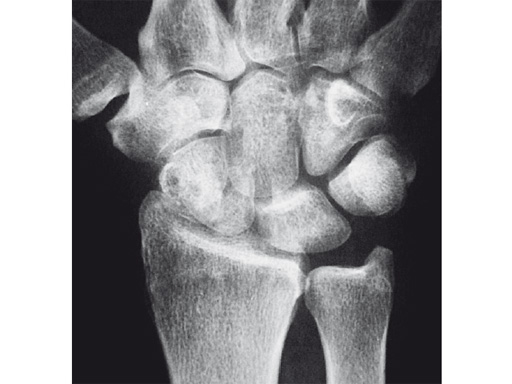

Fig 1ab Preoperative x-rays. Note the carpal collapse a a b nd DISI deformity.

Fig 1 X-ray shows SNAC wrist.